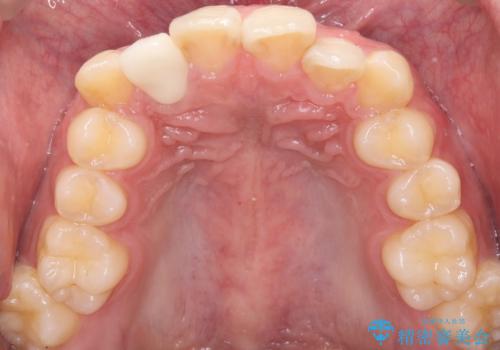

- 主訴:右上の前歯が何しなくても痛い

右上2番の歯に自発痛を認め、症状や歯髄診・レントゲン像から不可逆性歯髄炎と診断し、精密根管治療から歯冠補綴まで行うこととなりました。

初診時に歯髄診断を行い、不可逆性歯髄炎と診断し抜髄から補綴修復までの流れを説明し、精密根管治療、ファイバ-コア築造、オールセラミッククラウン(St)修復を行うこととしました。